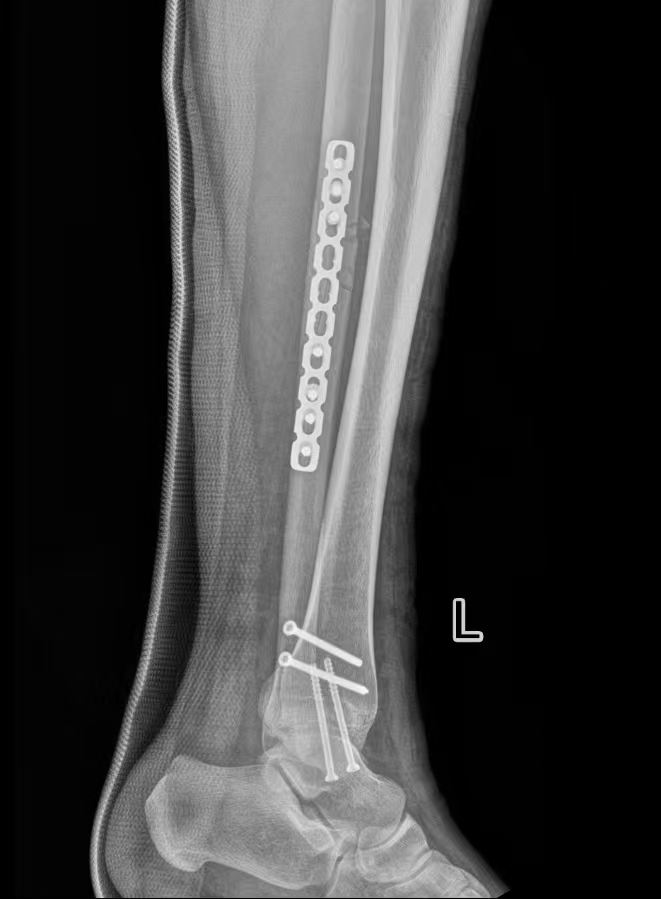

为保障诊疗安全,周占锋团队联合麻醉与围术期医学科、康复医学科开展术前综合评估,结合患者伤情与个体情况制定手术方案,并与患者充分沟通病情、治疗计划及注意事项,缓解其紧张情绪。

术中严格遵循骨科诊疗规范,完成骨折复位与固定,手术过程顺利。

术后,医护团队为患者制定个性化康复计划,开展伤口护理、疼痛管理与早期功能锻炼指导,定期监测恢复情况。

目前患者肿胀消退明显,踝关节功能逐步改善,整体恢复平稳。